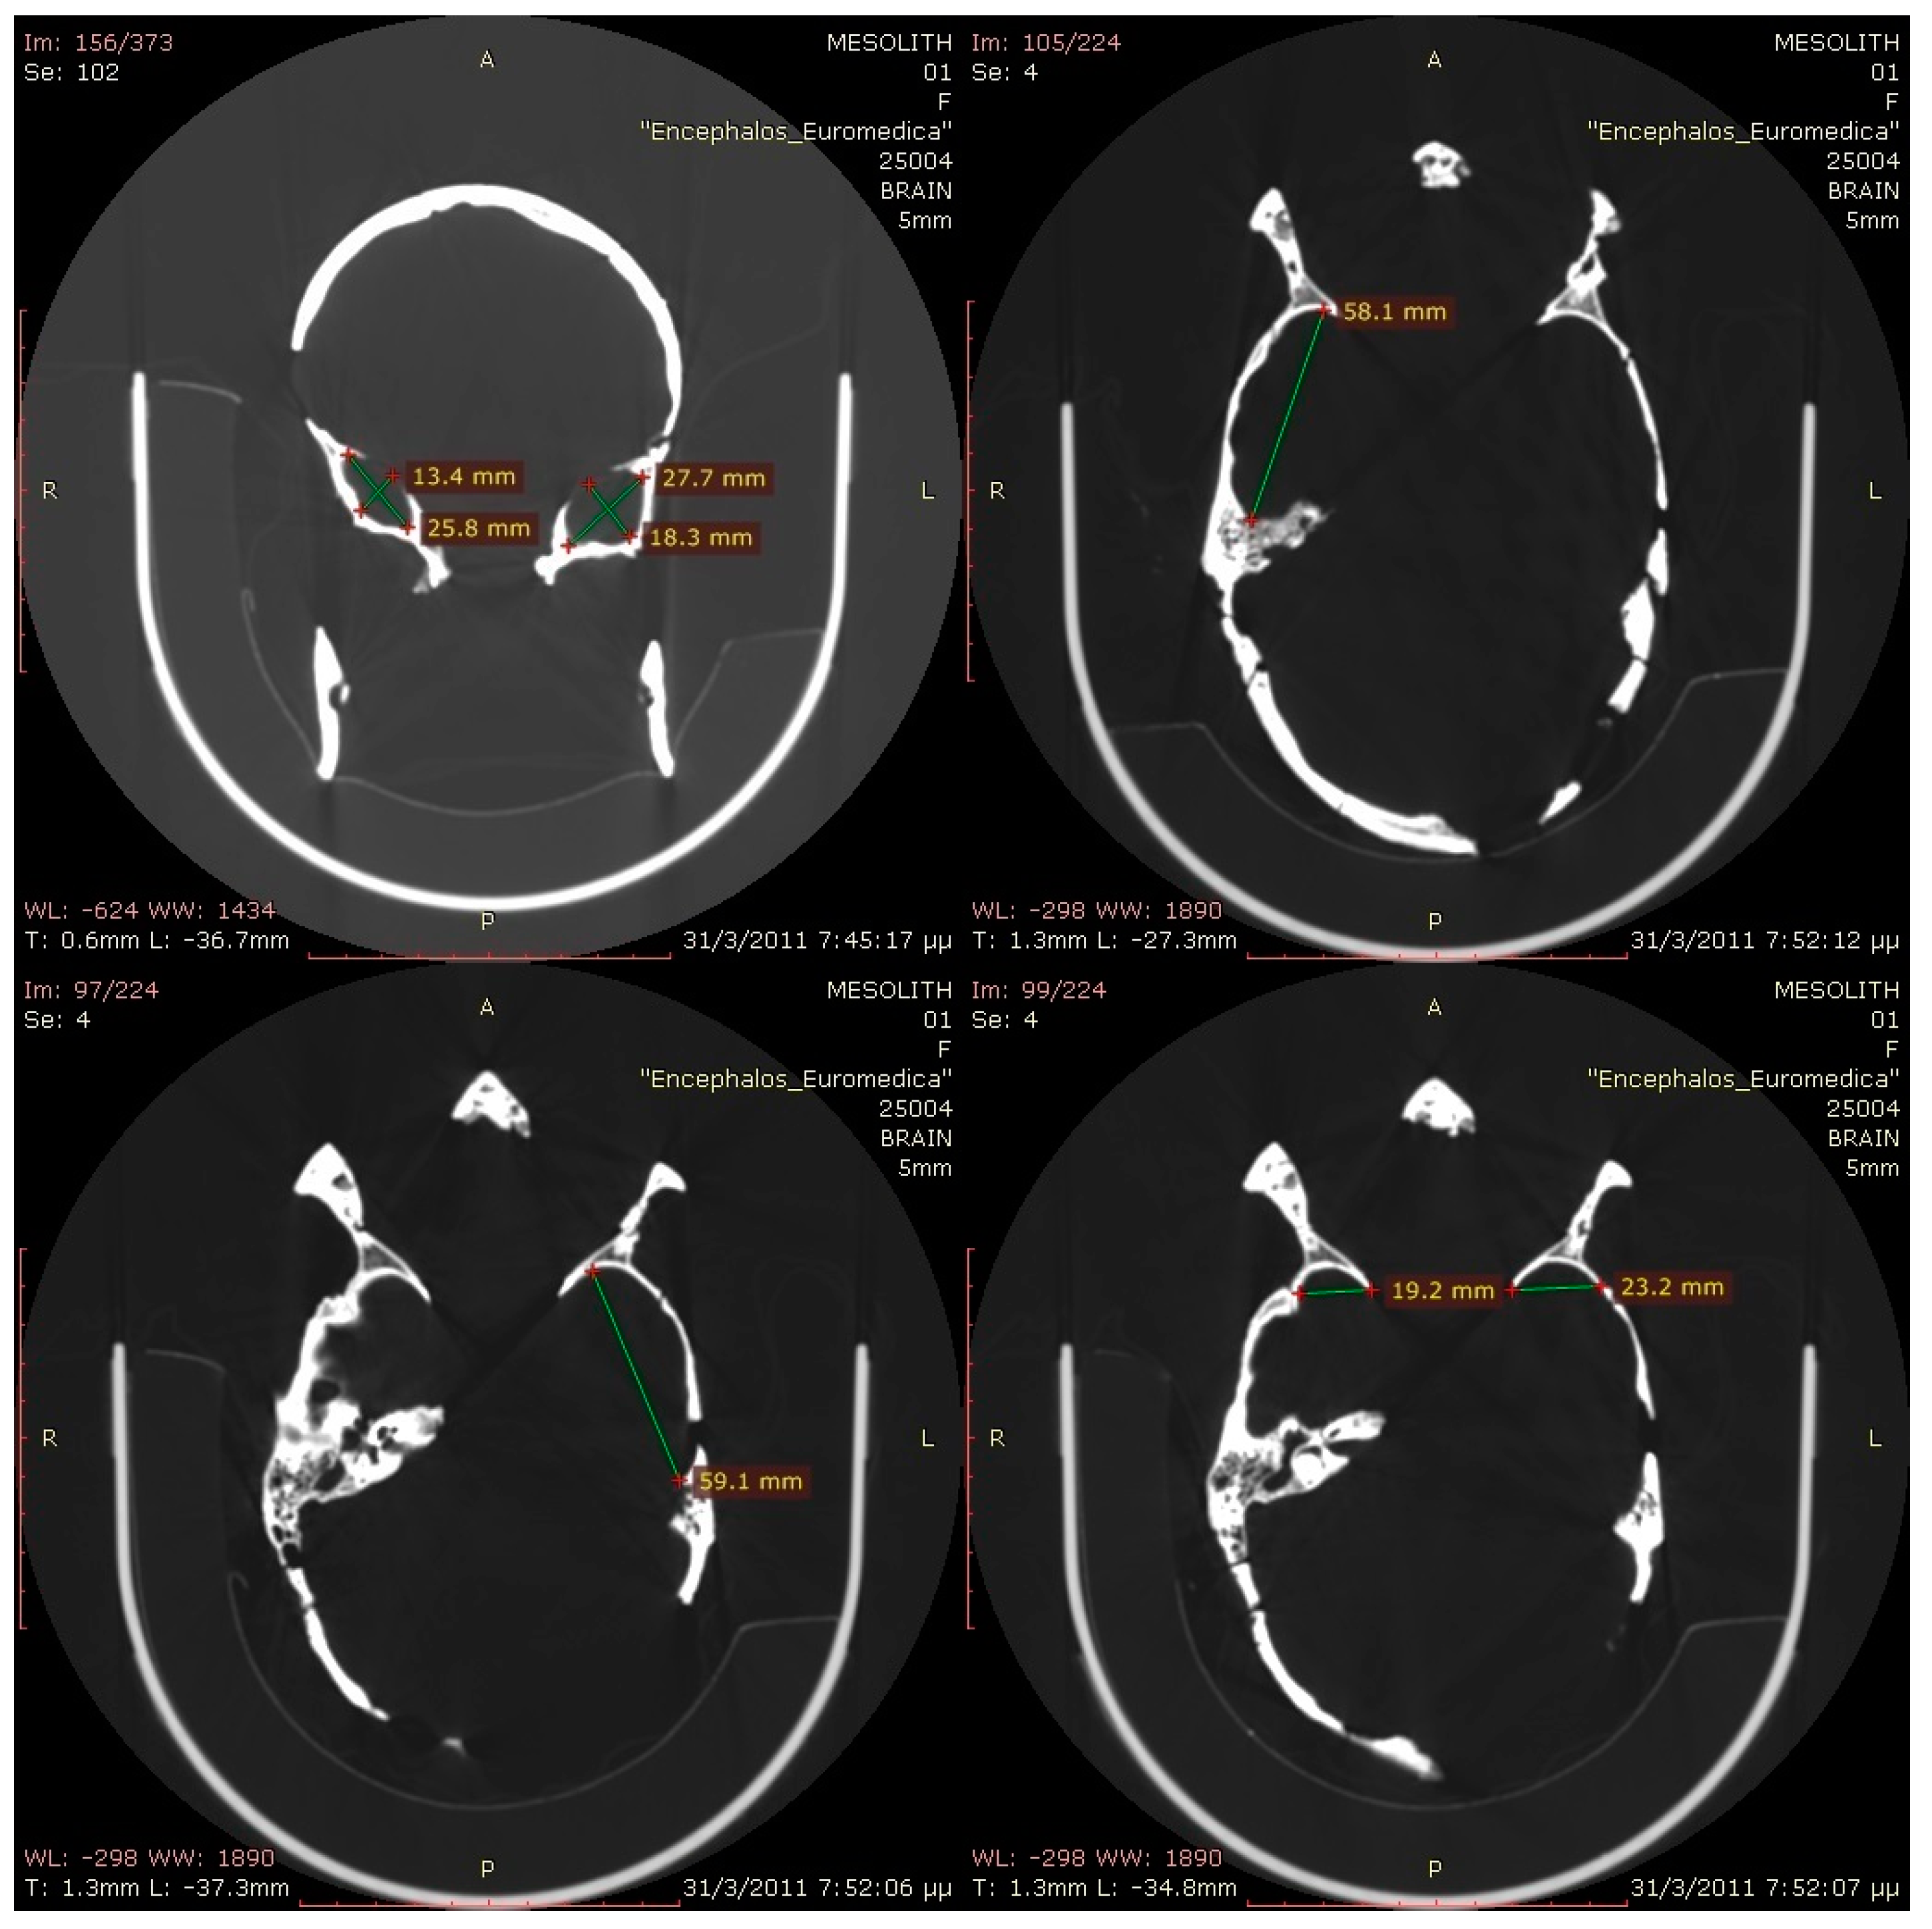

There is no doubt that a typical Homo sapiens individual (with no physical disabilities) who lived at about 7000 BC would have all the anatomical prerequisites to be able to speak (the Broca’s area, inferior frontal gyrus, sufficient brain volume, and sufficient descent of larynx are all elements identified well before this era) [45]. Indeed, the skull in our case exhibits all the aforementioned characteristics (Figure 3). However, due to bone deficits in the posterior cranial fossa, lack of foramen magnum, and a partial lack in the left temporal bone, any statistical measurement of the cranial volume would be subject to significant error. In addition, the aspect of the palate cavity showed that the larynx had descended in the neck, as in the adult human, thus allowing phonation. Therefore, all anatomical premises for speech exist in this case. In addition, a depression on the side of the forehead is related to a premature closure of the suture of the area.

Since the series of CT images covering the head were closely spaced (0.3 mm slice spacing), the 3D-reconstructed model of the skull reproduced very fine details of the original (Figure 7). The bounding box dimensions of the skull were 217 mm height, 134 mm width, and 186 mm depth. Interestingly, a substantial asymmetry between the left and right temporal cavity (in favor of the left) was observed and noted. The entire process of 3D printing took 66 h to be completed, and 479 cc3 of ABS and 236 cc3 of supported material were used. The skull was printed with a layer thickness of 0.245 mm, which corresponds to the highest level of resolution analysis of the Dimension SST 778 3D printer used.

Figure 3. Computerized tomography views of the skull.